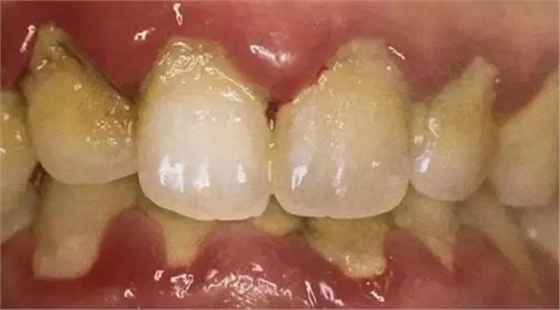

牙齦炎

區(qū)域:炎癥局限在牙齦軟組織中,主要由牙菌斑引起的。

癥狀:會(huì)造成牙齦紅腫、出血,點(diǎn)彩消失,但不會(huì)造成牙周袋也不會(huì)導(dǎo)致牙齒松動(dòng)。

在這個(gè)階段,牙齦炎還是可逆的,但是如果此時(shí)不進(jìn)行早期治療,不然牙齦炎就會(huì)進(jìn)一步發(fā)展成牙周炎,而且概率異常的高。